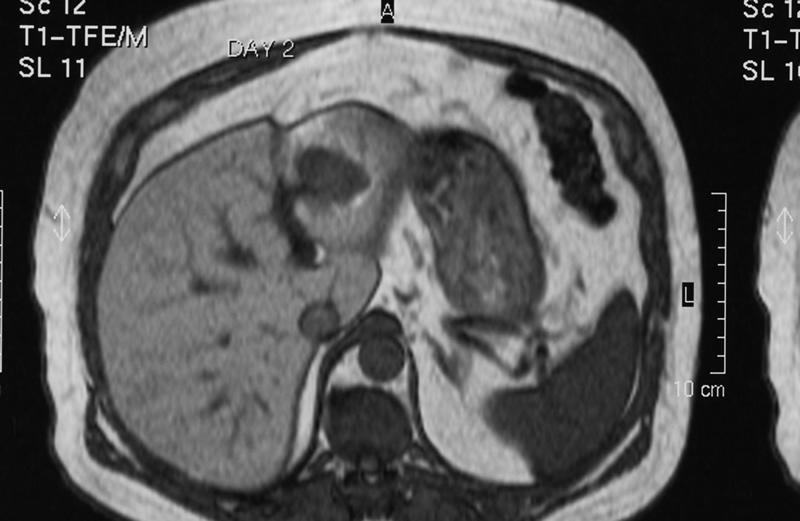

Figure 3 is an MRI showing lesion in segment 3 of the left hemi-liver.

MRI

Figure 3 - click image to enlarge